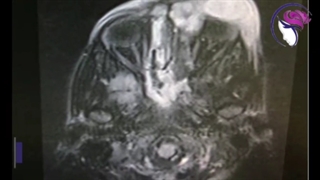

جراحی آندوسکوپیک انسفالوسل (وجود بافت مغز در بینی به واسطه نقص قاعده جمجمه) در کودک 9 ماهه توسط دکتر امین آمالی متخصص گوش و حلق و بینی و عضو هیئت علمی دانشگاه علوم پزشکی تهران